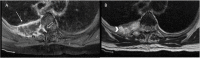

Annotated axial fat-saturated T1-weighted contrast-enhanced MRI of the thoracic spine showing a peripherally enhancing lesion centred in the posterior right fourth rib (closed arrow) with an enhancing soft tissue component that invades the adjacent pleural space, right neural foramen and right lateral epidural space of the spinal canal (open arrow) and axial T2-weighted MRI of the thoracic spine showing areas of T2 hyperintensity within the lesion (arrow head) suggesting a fluid/mucinous component.